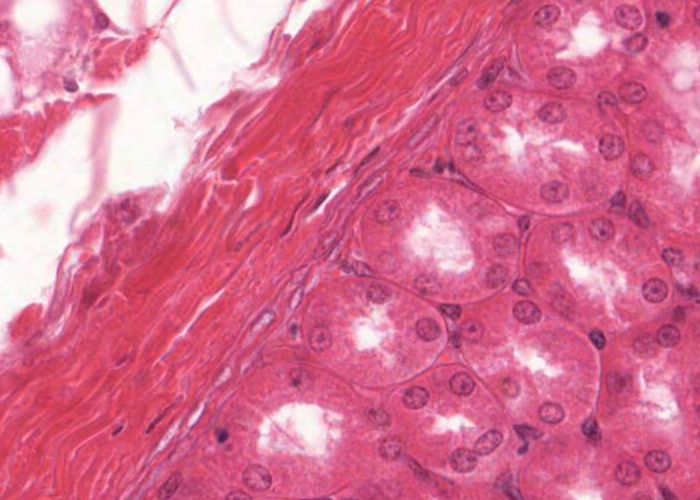

You will know where to locate the kidney capsule from the previous item of a section through a kidney lobule but now you can see details of the structure of this capsule in this image taken at a much higher magnification. The surface of the kidney is a capsule consisting of two distinct layers of connective tissue. The outer layer is typical collagen fibres and fibroblasts (each with a very thin, elongated nucleus). The inner layer is more cellular as it is occupied by many myofibroblasts each with an elonged but paler nucleus. The functional significance of these myofibroblasts is unknown. Within the hilum of the kidney this capsule becomes continuous with the connective tissue linings of the calyces and the renal pelvis. Just under the capsule you can identify a number of profiles of proximal convoluted tubules.